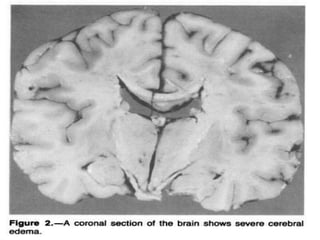

Def: Cerebral edema resulting from urea removal

from the blood more rapidly than from the CSF

and brain tissue generating a urea osmotic

gradient responsible for water moving into brain

cells.

Disequilibrium Syndrome Def: Cerebraledema resulting from urea removal from the blood more rapidly than from the CSF and brain tissue generating a urea osmotic gradient responsible for water moving into brain cells.